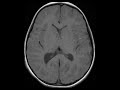

Tuberous Sclerosis

There are multiple T2 FLAIR hyperintense non-enhancing cortical and subcortical lesions as well as multiple subependymal nodules which demonstrate heterogeneous T2 FLAIR signal and enhancement with increased susceptibility. Findings are compatible with the “tubers” or hamartomas of tuberous sclerosis with the subependymal nodules demonstrating increased susceptibility compatible with calcification. In addition to these findings, other imaging features include areas of “cystoid” degeneration and white matter migration lines. The classic clinical picture is that of facial angiofibromas, seizures, and mental retardation.